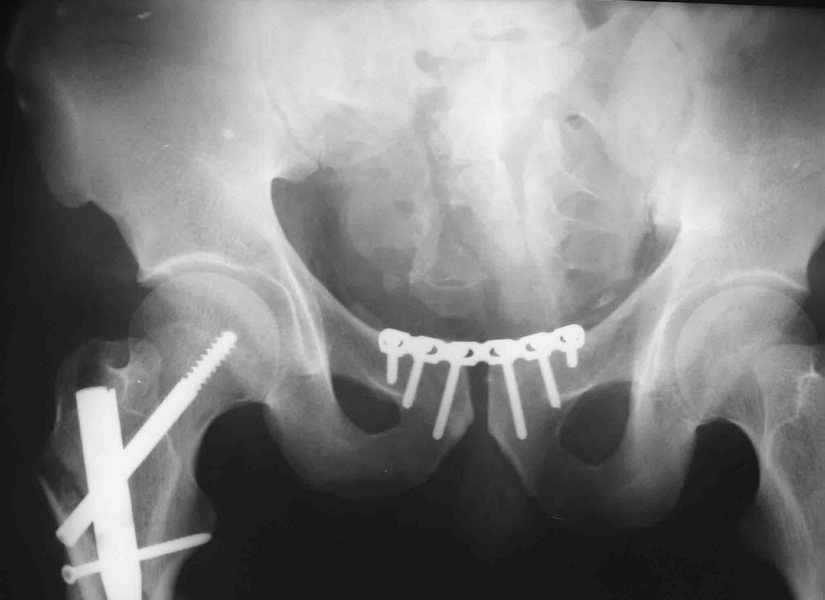

извините за опоздание , вот фотографии

Репозиция действительно очень неплохая, но чтобы уменьшить риск развития поздней нестабильности, в такой ситуации лучше выполнить синтез лонного сочленения пластиной и оставить аппарат месяца на 2.

В представленном случае повреждение несомненно ротационное и реальный диастаз как раз около пограничных 2,5 см, репозиция идеальная, достигнута в первые дни после травмы. Я бы ограничился 3 мес фиксации в аппарате с ограничением нагрузки первый месяц, и функциональными снимками в 6 -8 недель.

ПЕРЕСМАТРИВАЛ РАЗНЫЕ СНИМКИ И НАШЕЛ НА ЭТУ ТЕМУ ФОРУМА СНИМОК. БОЛЬНОЙ БЫЛ ПРООПЕРИРОВАН НА ПРАВОЕ БЕДРО ПОСЛЕ ЧЕГО СДЕЛАН ТАЗ В ЦЕЛОМ. ВОТ ЧТО НАШЛОСЬ.

КАКОЕ ВАШЕ МНЕНИЕ О ТАКТИКЕ.

ДУМАЮ ПРОШЛО ОКОЛО 10 ДНЕЙ.